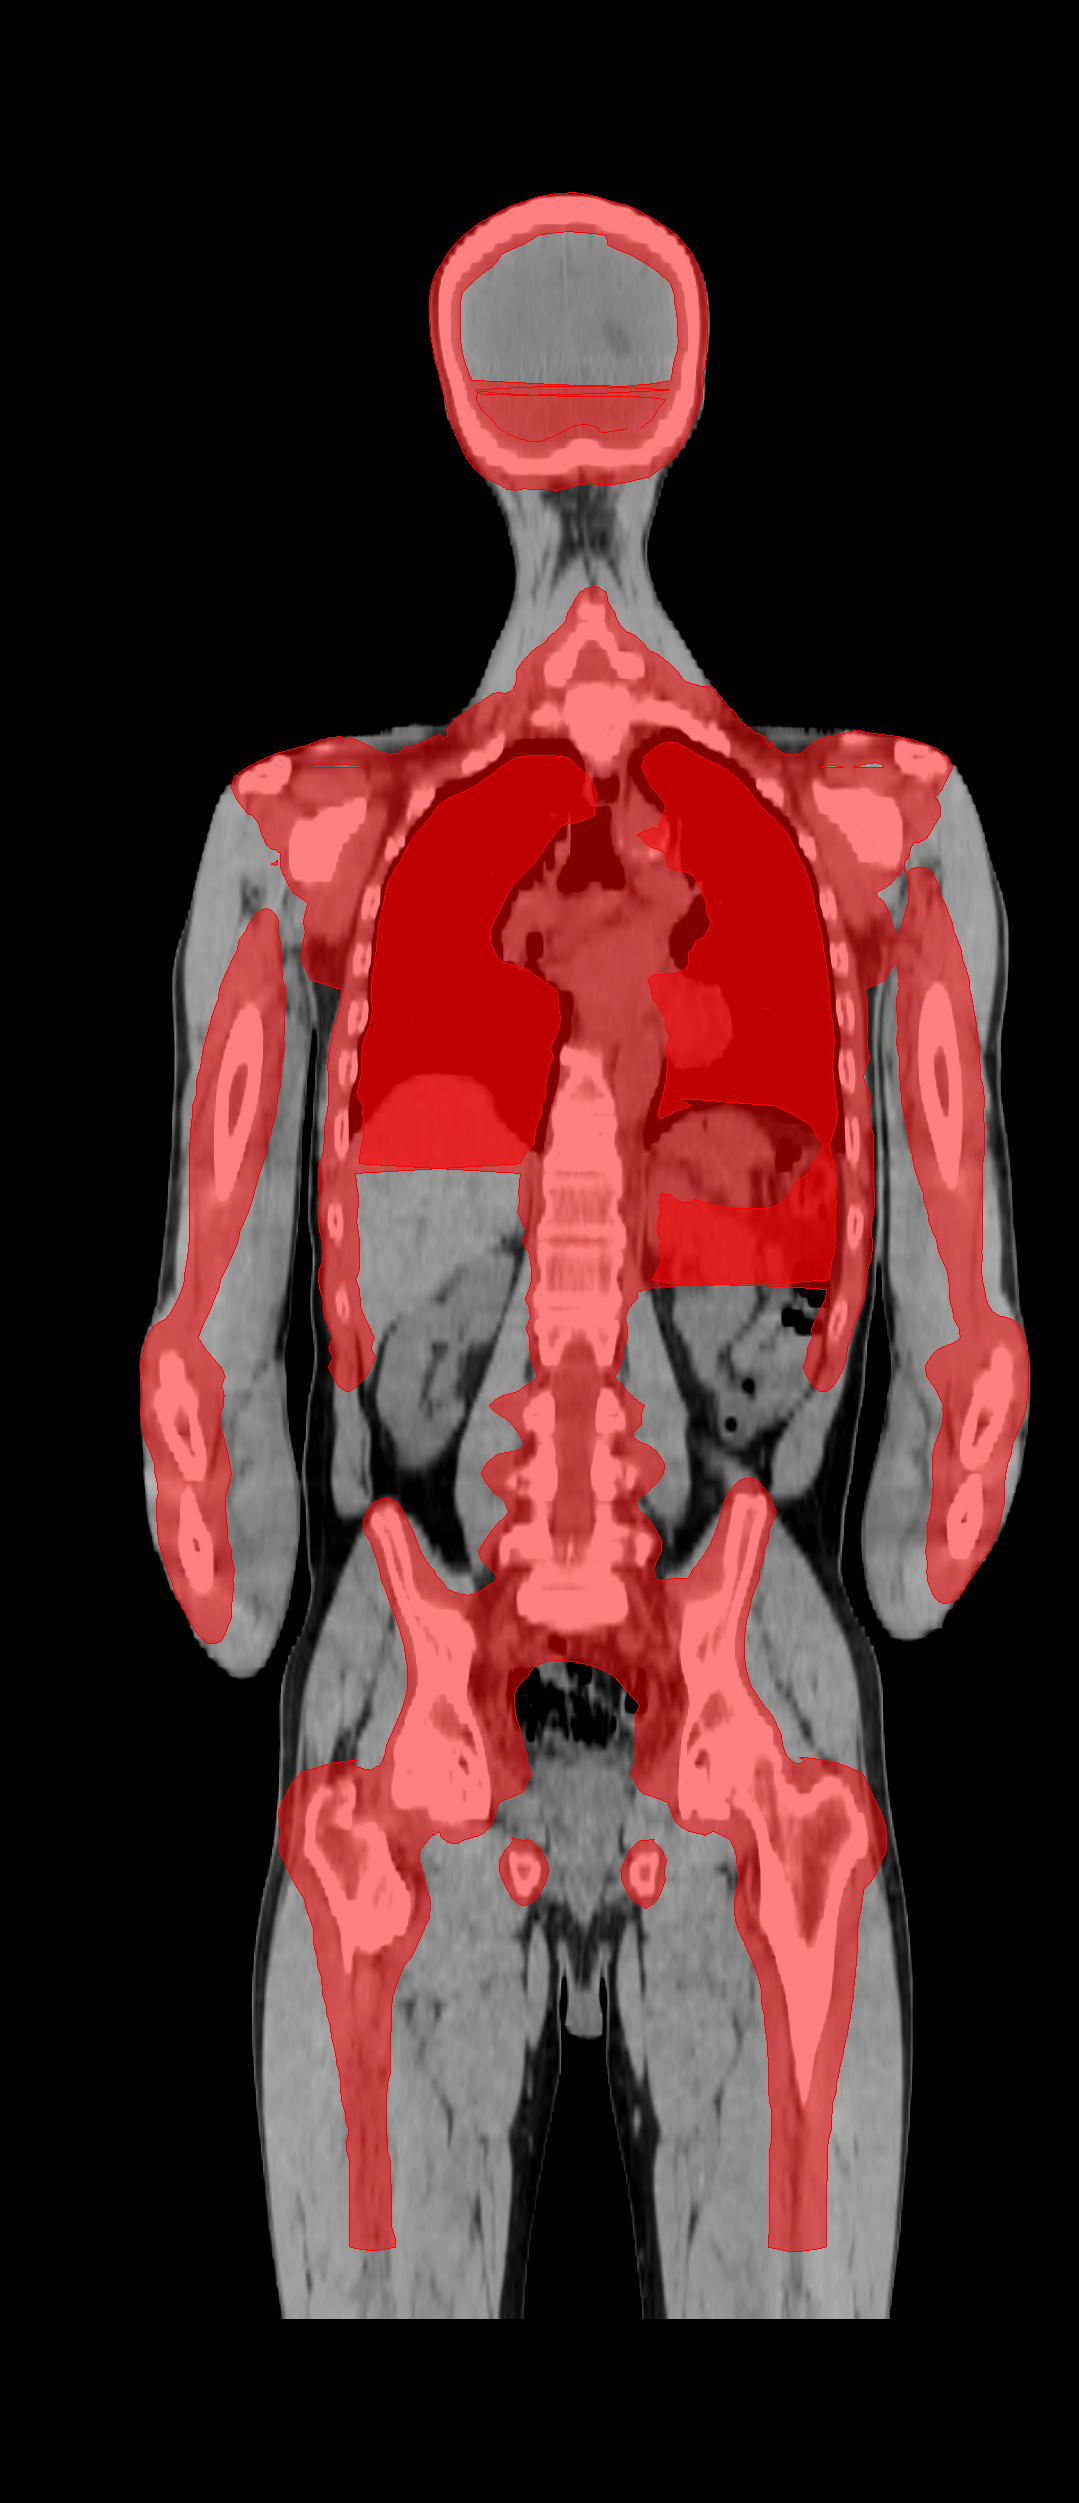

The TMLI clinical target volume (CTV) encompassed the bone marrow (CTV_BM), spleen (CTV_Spleen), and all lymph node chains (CTV_LN). The CTV_BM was considered equivalent to the skeletal bones, with the chest wall added to the ribs to account for breathing motions. To minimize oral cavity toxicity, the mandible was excluded from the CTV_BM, along with the hands, which have an extremely limited bone marrow presence. The total planning target volume (PTV_Tot) was defined as the union of three PTVs, derived from the isotropic expansion of three corresponding CTVs, as follows: (i) PTV_BM = CTV_BM + 2 mm (+8 mm for arms and legs) to account for setup margin; (ii) PTV_Spleen = CTV_Spleen + 5 mm to account for breathing motions and setup margin; and (iii) PTV_LN = CTV_LN + 5 mm to account for target residual motion and setup margin.

Figure 1 presents an example of the PTV_Tot defined for a patient. The dataset contains the CT scans of each patient and the corresponding PTV_Tot structure stored using the DICOM-RT format. In this study, we trained a model to directly segment the PTV_Tot target. Unlike other PTVs and CTVs, the PTV_Tot is the only target consistently annotated by ROs for all 100 patients included in the dataset.